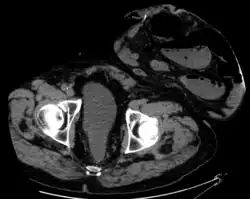

A colostomy is an opening (stoma) in the large intestine (colon), or the surgical procedure that creates one. The opening is formed by drawing the healthy end of the colon through an incision in the anterior abdominal wall and suturing it into place. This opening, often in conjunction with an attached ostomy system, provides an alternative channel for feces to leave the body. Thus if the natural anus is unavailable for that function (for example, in cases where it has been removed as part of treatment for colorectal cancer or ulcerative colitis), an artificial anus takes over. It may be reversible or irreversible, depending on the circumstances.

Placement of the stoma on the abdomen can occur at any location along the colon, but the most common placement is on the lower left side near the sigmoid where a majority of colon cancers occur. Other locations include the ascending, transverse, and descending sections of the colon.[4]